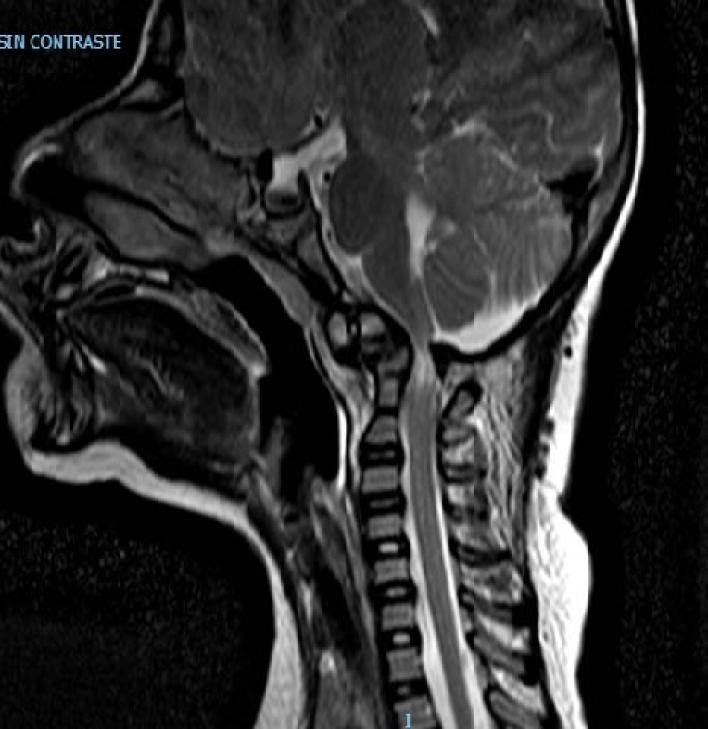

Se decide internación por síndrome medular agudo, y se realizan estudios por imágenes donde se observa lesión medular con mielomalacia debido a mal formación en charnela con inestabilidad atlanto axoidea y estrechamiento del foramen (Figuras 1, 2 y 3). En tomografía se observa agenesia del arco posterior del atlas con displasia de macizos laterales (Figura 4).

Figura 2: Resonancia sagital preoperatorio

Figura 3: Resonancia columna completa preoperatorio